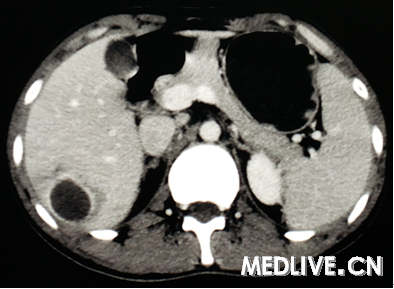

男,26岁,右上腹部疼痛伴畏寒发热3天。

图3为CT增强静脉期,

右上腹痛伴畏寒发热提示有感染存在,CT为囊性病变,动脉期囊腔周围有水肿,静脉期囊腔边缘增强,囊内无增强排除血管瘤;囊内无子囊,无分隔可排除肝包虫感染。最终诊断为肝脓肿。

诊断:肝脓肿。 依据:发热,畏寒考虑感染性疾病,患者右上腹疼,上腹部CT肝右叶可见空腔,周围水肿带,增强可见强化,符合肝脓肿影像。 鉴别:肝囊肿并感染,肝结核。

上腹痛伴畏寒发热提示有感染存在,排除肝囊肿;CT示球形囊性病变,动脉期囊腔周围有水肿,静脉期囊腔边缘增强,囊内无增强排除血管瘤;囊内无子囊,无分隔可排除肝包虫感染。诊断考虑肝脓肿。

CT可见肝内囊性病变,边界清,囊内呈液性暗区(无增强),无分隔,囊腔周围有水肿,综合上述CT表现诊断为肝脓肿。